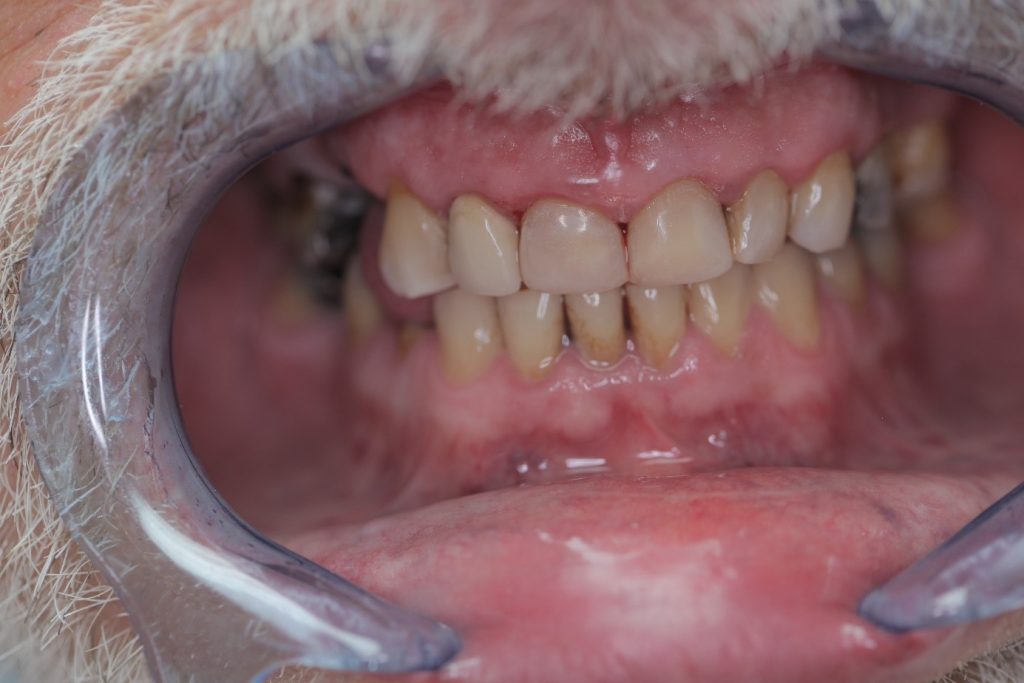

Multiple front teeth fillings, edge restorations using Asteria composite (Case presentation) (54)

A male patient, aged 67, reported to our clinic with the aim of having his condition assessed. He received a detailed treatment plan for his dental problems, which meant the fabrication of a full-arch bridge for his upper jaw. During the patient’s 2-day stint in Hungary we tried to focus on dealing with the most critical problems.

The front teeth were filled using Tokuyama Asteria Estelite filling materials.